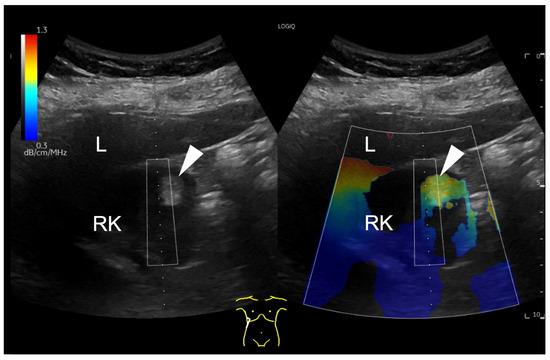

Findings in which the measurement was influenced by given factors, findings without the possibility of a measurement, and findings with no possible measurement but with a positive, fat-rich visual finding in the colour map were recorded in the database separately. An example of a focal renal lesion that was not accessible for UGAP measurement is shown in Figure 2.

Figure 2.

B-mode ultrasound of the right kidney (RK), displaying a focal hyperechogenic lesion (arrowhead) in the cortex, which is barely included in the colour coded attenuation map. The ROI box on the right side of the map can be only moved horizontally due to methodological reasons. Due to the superficial localization of the small renal lesion, the attenuation colour map is only partial applicable (arrowhead).